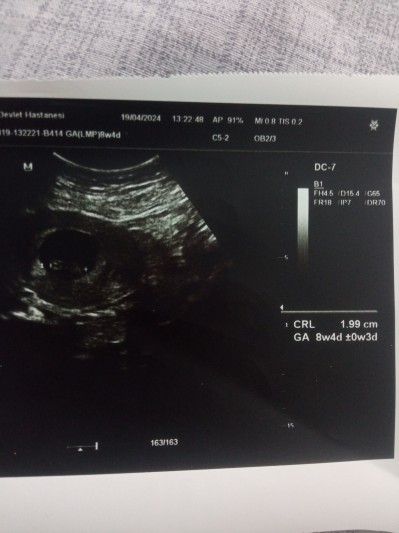

Kizlar şuan 10+1 haftalık olacağıma dün doktor dedi 8+4 dedi neden haftam geri gelio

Gebelik haftası 8+5

Geç döllenme olmuş doktorunun demesi gerekiyordu benim de 8+4 de 6+3 göründü bebek adet tarihimi iki hafta ileriye aldılar

Keseyı paylastım yukarda bakarmısın acaba

Bktim canım benim ilk göründüğünde 4.7 mm di 6+4 olarak yazmış doktor ama ben son adete göre 8 buçuk haftadaydim senin de bebek daha küçük daha çok yeni yani degistirmezlerse bile sen guzelce beslen o büyüdükçe haftasını yakalar

Benım geçen hafta gece7mmsçdı dün 10 mm olmuş boş gebelık olabılır dedı doktor takıpte kalman lazımmdedı bılmıyom kafam çok bulanık